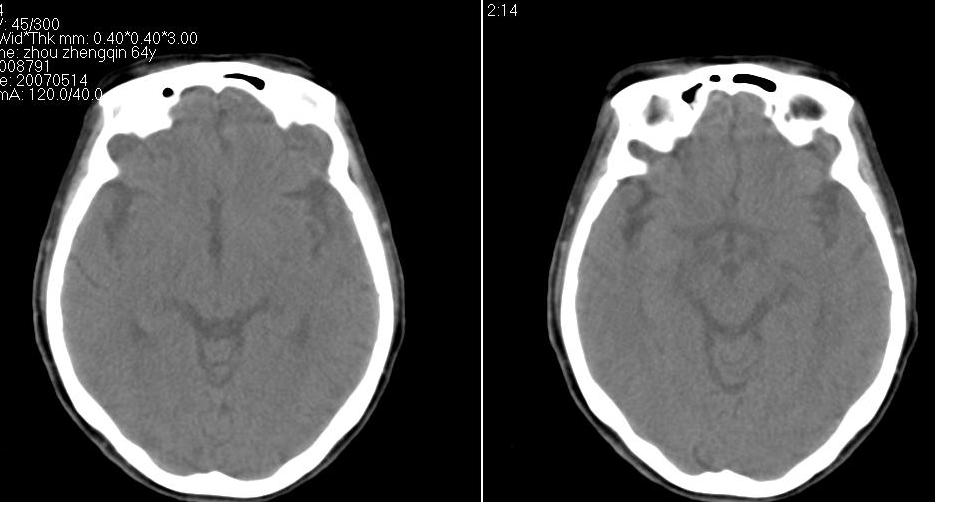

以下是引用zhw974247在2007-5-14 19:34:00的发言:[br]泪腺肿瘤在眶原发性肿瘤中发病率最高,而泪腺混合瘤又是其中最常见者,有良性及恶性二种。良性泪腺混合瘤多见于中年人,病程长,来源于泪腺管或腺泡,也可以起源于副泪腺及先天性胚胎组织残留(泪腺原基)。恶性泪腺混合瘤缺少或无完整的包膜,肿块与眶缘发生粘连,粘连部眶缘有压痛。瘤组织除有良性泪腺混合瘤的结构外,还有癌变的组织构成。瘤组织向眶内浸润,破坏骨质,可发生全身转移,严重者向颅内转移,危及生命。[br]